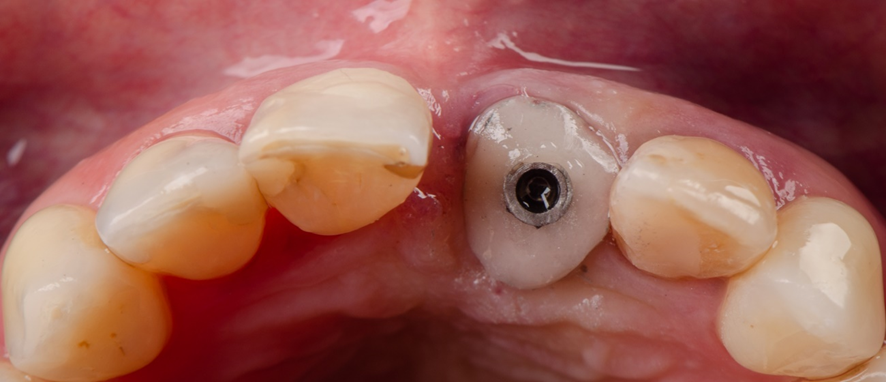

Aspecto inicial intra-oral:

Vista oclusal do cicatrizador personalizado mantendo o arcabouço gengival.